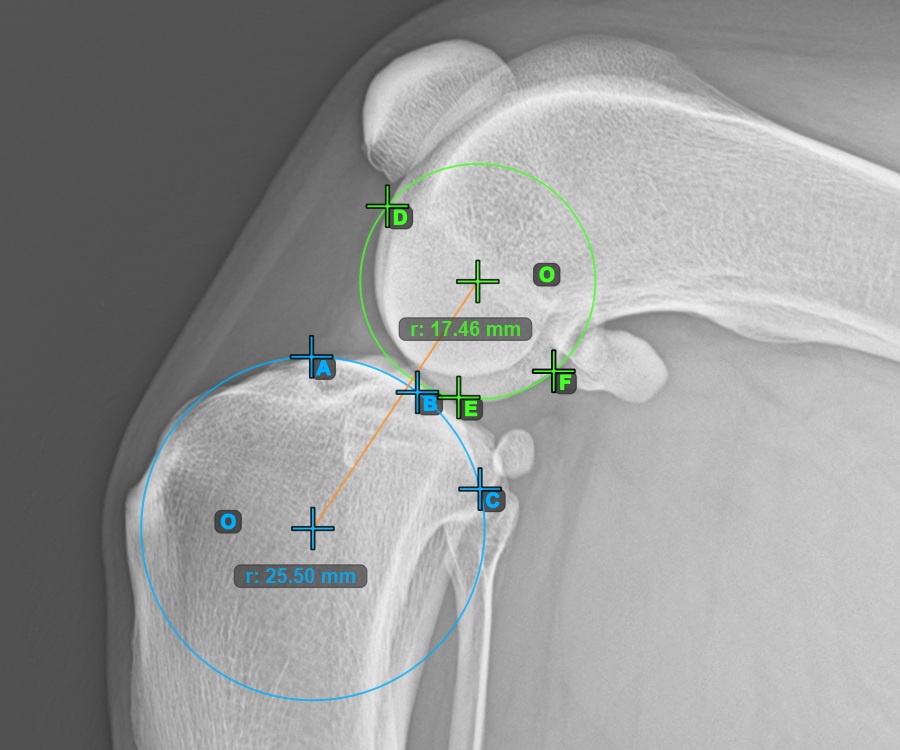

Markieren Sie einen Punkt vor dem Gelenk auf der gemeinsamen Tangente zwischen den beiden Kreisen. Eine Linie wird automatisch durch den markierten Punkt gezogen.

Das Bild unten zeigt die typische Platzierung des Punkts auf der gemeinsamen Tangente zwischen den beiden Kreisen.